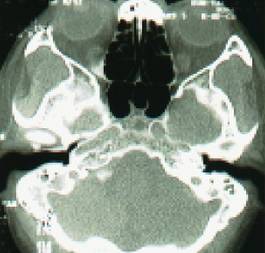

- 副鼻窦X线检查,CT(冠状位、轴位)检查已常规应用。

正常鼻窦CT

鼻窦炎轴位CT

鼻窦炎冠状CT